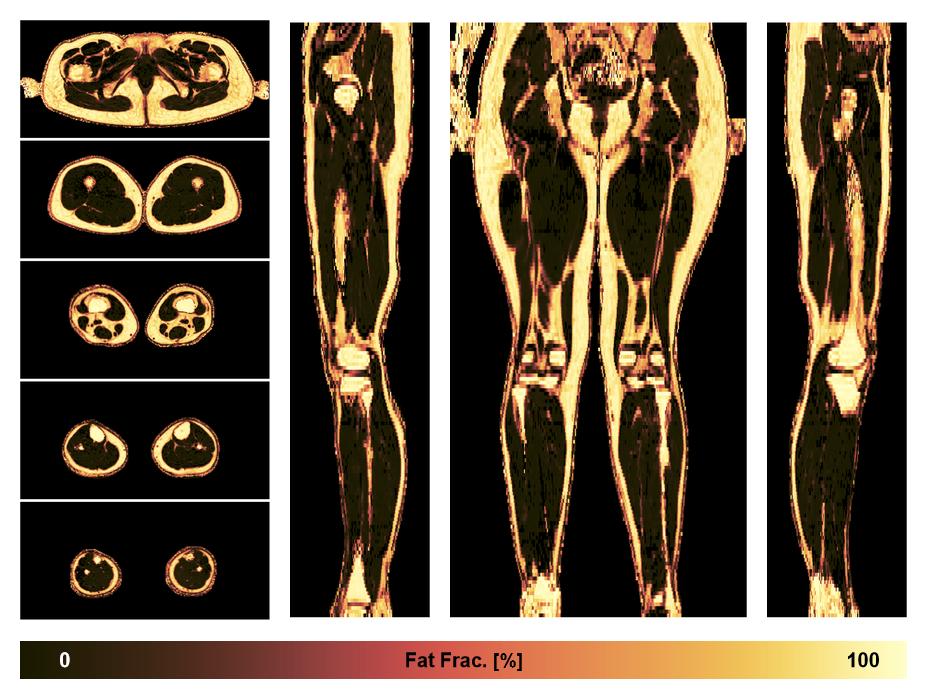

• Fat fraction

The fat fraction of the lower extremity obtained from the dixon reconstruction for muscle water fat quantification.